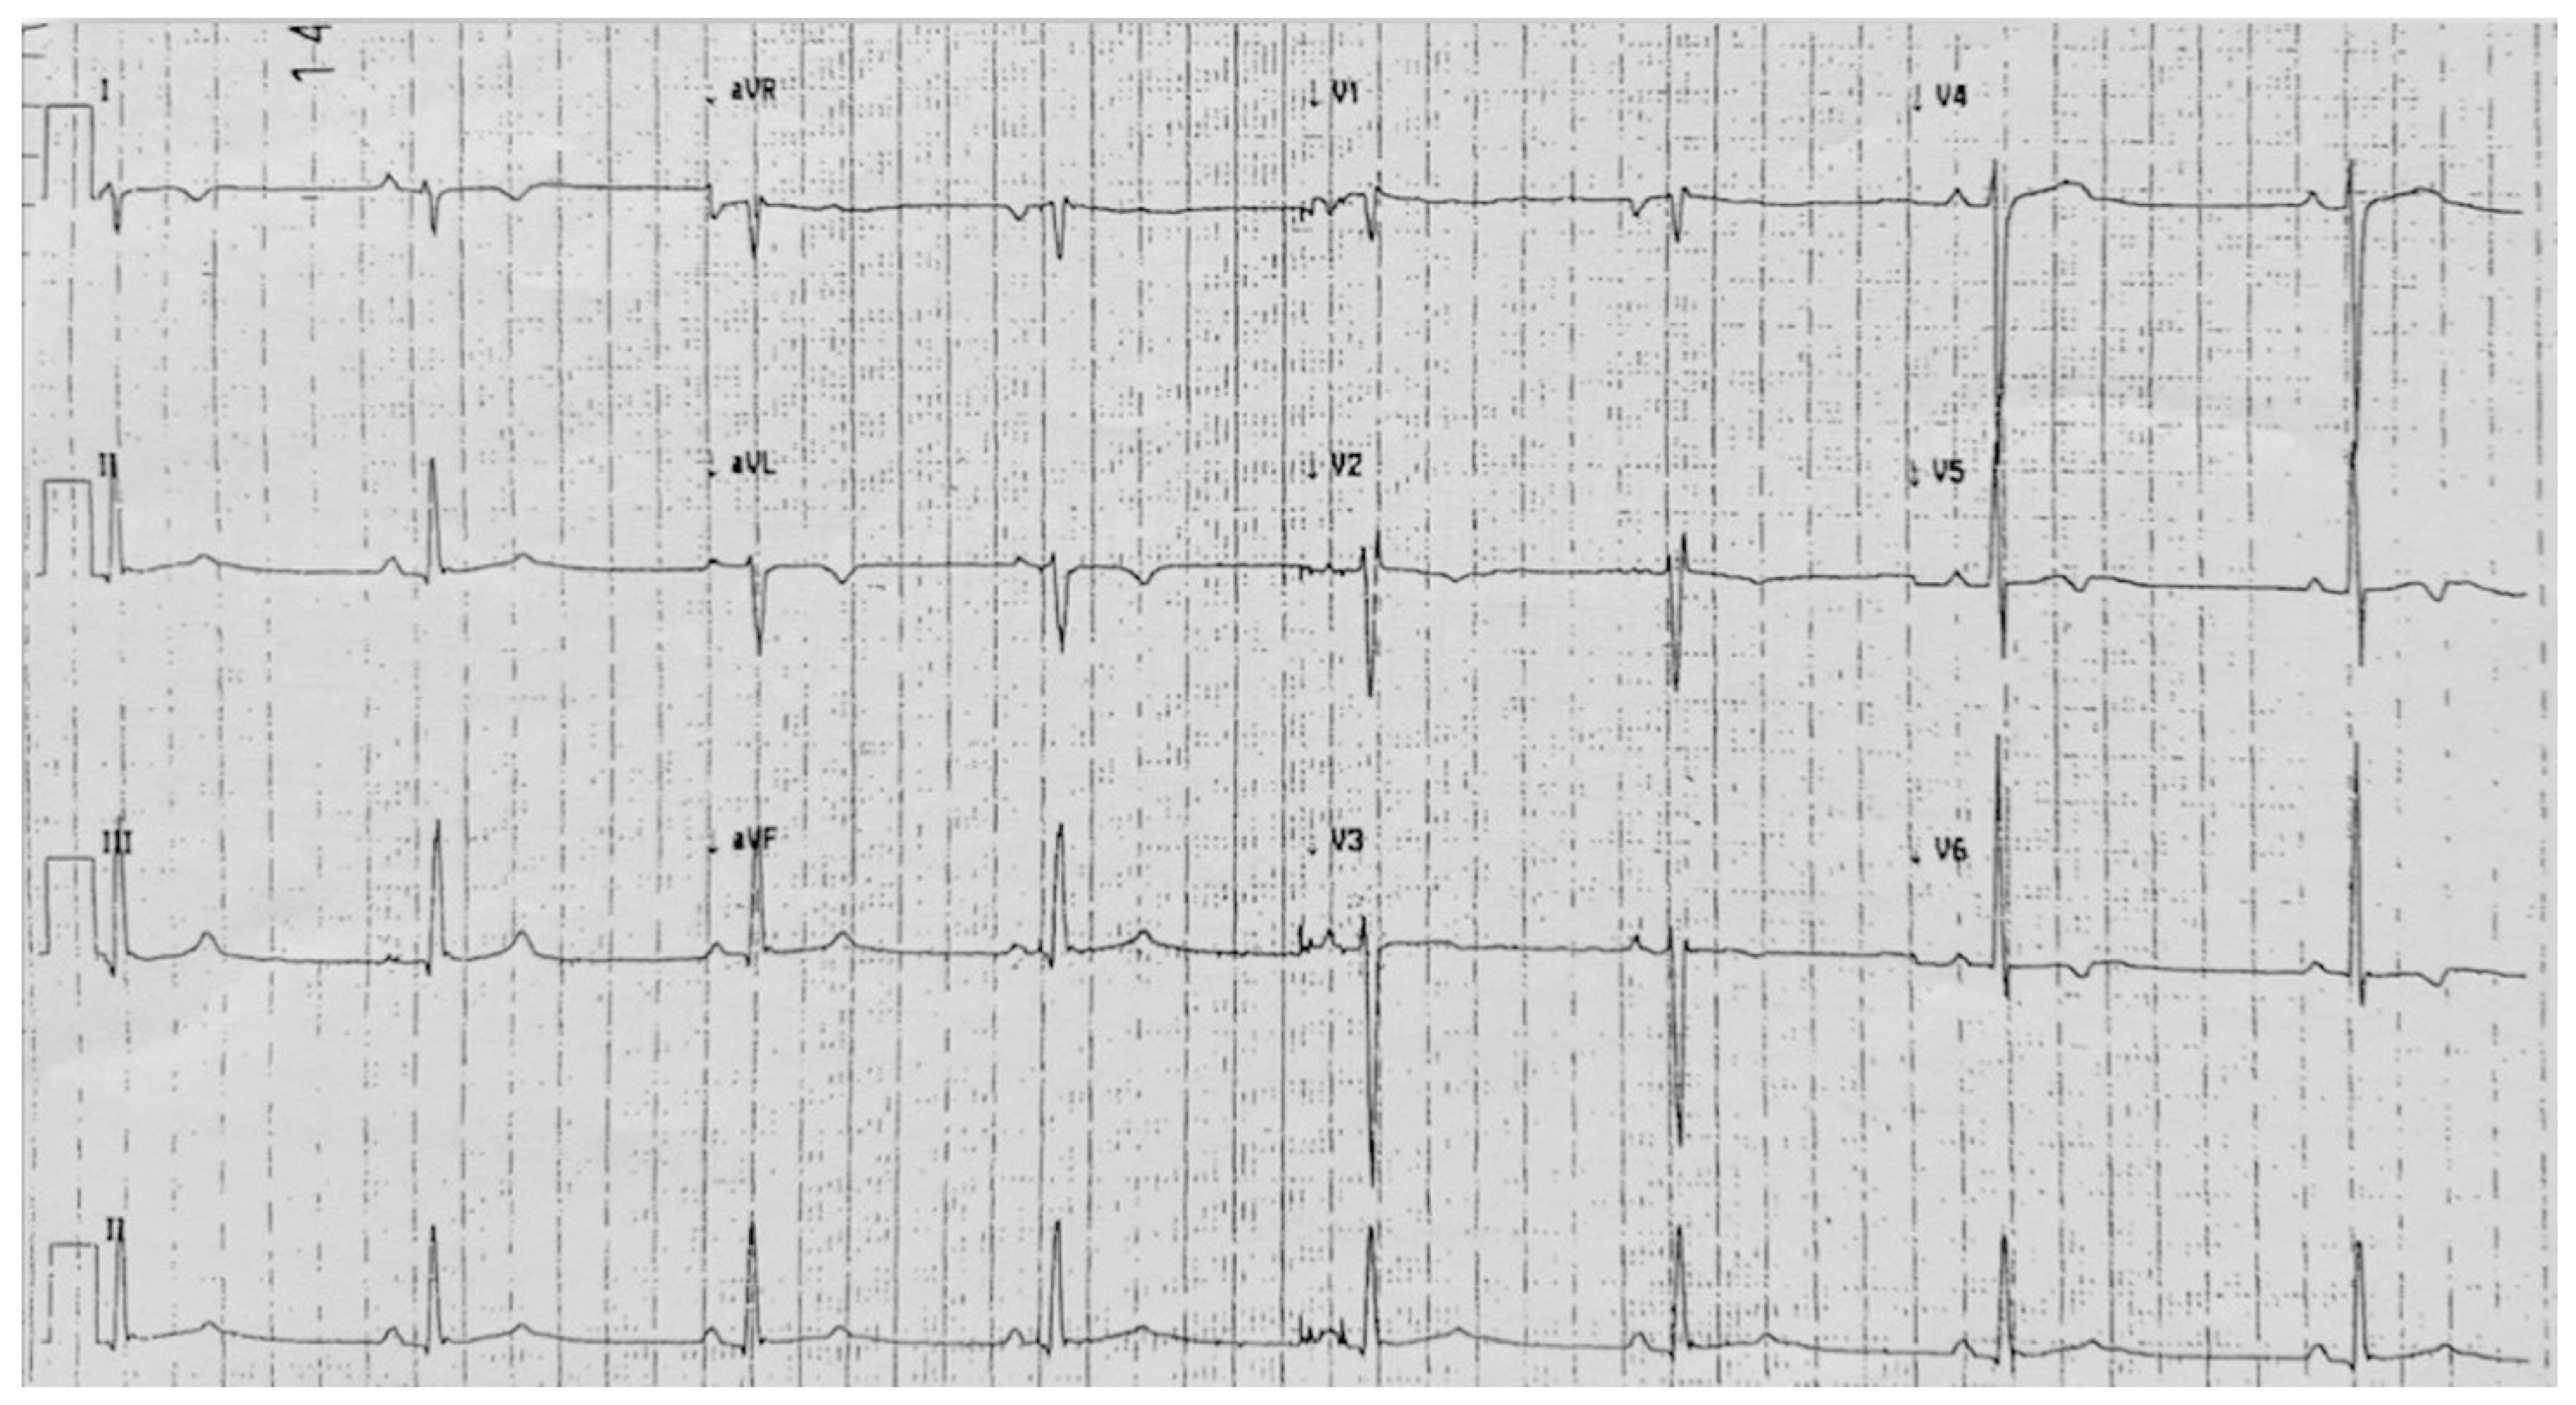

5. Case 4